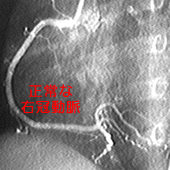

具体的には、こぶができるのですが、こぶ自体が破裂したりすることはほとんどありません。しかし、こぶが治っていくとき、ギザギザ・デコボコに治って、狭いところを作ってしまうことがあるのです。

皮膚にできた大きな傷が、デコボコに治ることがあります。あれと同じことが冠動脈に起こってしまうのです。

極端な場合は、詰まってしまうこともあります。そうすると、いわゆる「心筋梗塞」です。場合によっては、死に至ります。